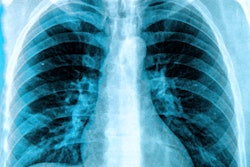

An investigation of Portsmouth Hospitals National Health Service (NHS) Trust regarding mistakes in checking the x-rays of two patients who later died has found these mistakes were within an acceptable error rate, according to a BBC report.

The finding is part of a larger inquiry into the trust, specifically Queen Alexandra Hospital, which began last December by the Care Quality Commission when it was discovered that thousands of x-rays acquired there were not being read by expert radiologists because of a backlog of work.

The two patients died after junior doctors missed lung cancers, but the trust avowed the performance of these doctors did not result in increased rates of harm to patients, the BBC reported. An assessment conducted by the consultancy firm Verita for the trust agreed, stating the hospital's radiology department had deprioritized expert reviews of x-rays after determining the risk to patients was small, and the junior doctors had "performed within the accepted error rate of a qualified radiologist," according to the BBC.